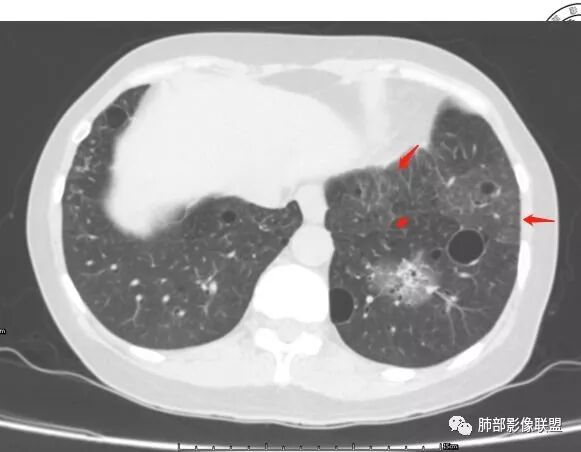

胸CT:1.双肺多发囊性变,以中下肺为主,病变边缘可见肺动脉,部分囊内可见分隔及肺动脉,双下部分肺野周围可见小叶中心结节及树丫征。

患者中年女性,因右眼红痛1天就诊。胸CT:双肺多发囊性变及结节影,囊以中下肺为多,部分囊内可见分隔及肺动脉,结节部分为实性,部分为混合性,边缘光滑,未见明显毛刺、棘突、胸膜牵拉及血管集束征象。双中下可见支气管扩张及树丫征。淋巴结无明显肿大。综合考虑:一元淋巴细胞间质性肺炎。多元鉴别肺腺癌并转移等恶性病变。

中年女性,因“角膜炎”入院,自用眼液2年,(眼干?)肺部:双肺多发类圆形薄壁气囊+实性结节+GGO,下肺分布为主,纵隔淋巴结肿大,考虑淋巴系统增殖,LIP可能性大,可能继发于干燥综合症;左肺下叶的混合磨玻璃结节形迹可疑,边界清晰,内部疑似空泡,扩张扭曲支气管,极像肺癌,伴双肺转移?待排吧

左肺下叶混杂密度病灶,其内可见空泡,周围ggo清楚,考虑浸润性腺癌。双肺散在多发薄壁囊腔和实性结节,以胸膜下及血管旁分布位于,气囊可见血管贴边征,双肺小叶间隔及中央间质增厚,局部可见磨玻璃影及树芽征,纵隔内淋巴结肿大,考虑LIP

综上,考虑左下肺浸润性腺癌+LIP

双肺多发大小不等囊腔,可见薄壁,部分囊腔内可见血管影,伴双肺多发结节,结合患者眼病及类风湿病史,考虑LIP可能大。另左肺下叶磨玻璃结节,边界清晰,内可见空泡,伴纵膈多发肿大淋巴结,不除外浸润性腺癌可能。

双肺下叶分布为主的间质改变(磨玻璃影、小叶间隔增厚)、散在气囊影(常有血管贴边)、边界不清小结节